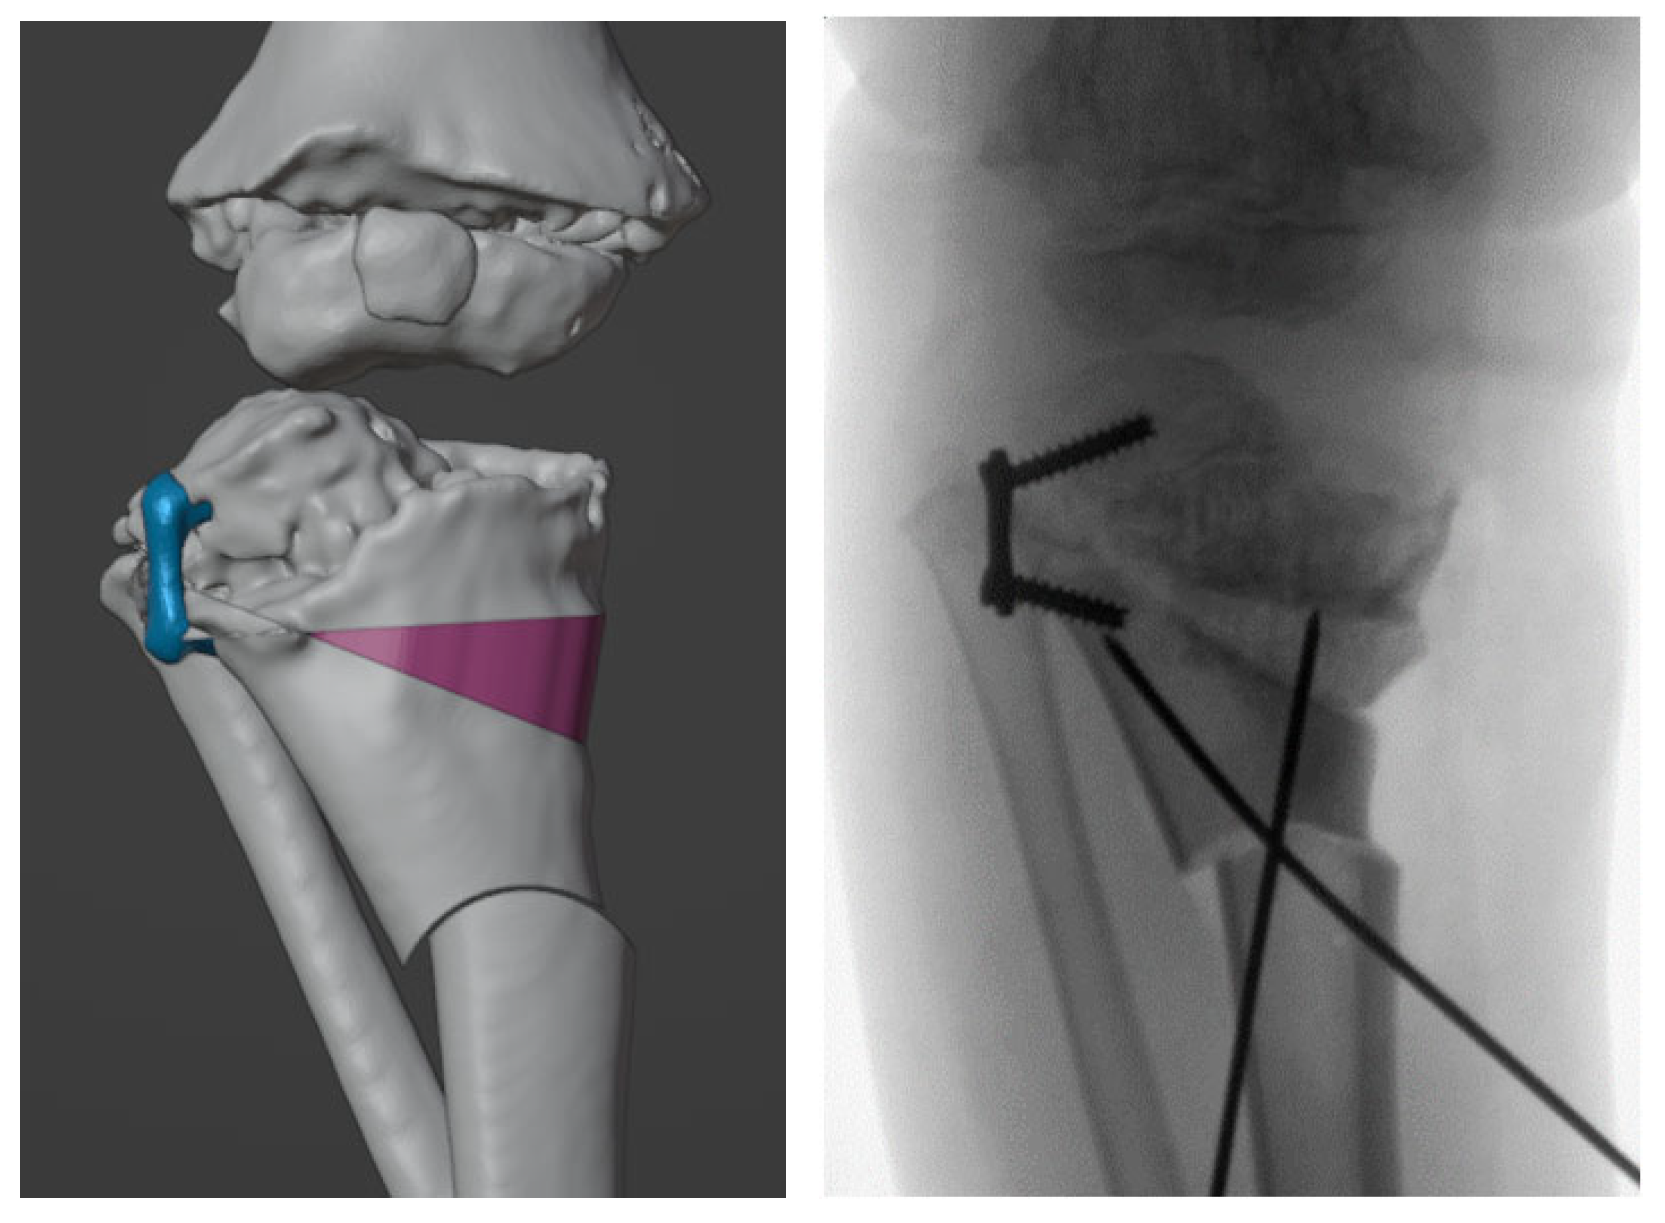

2.4. Design and 3D-printing of the Patient-Specific Surgical Instrument

2.5. Design and Processing of the Patient-Specific Bone Allograft

3. Results